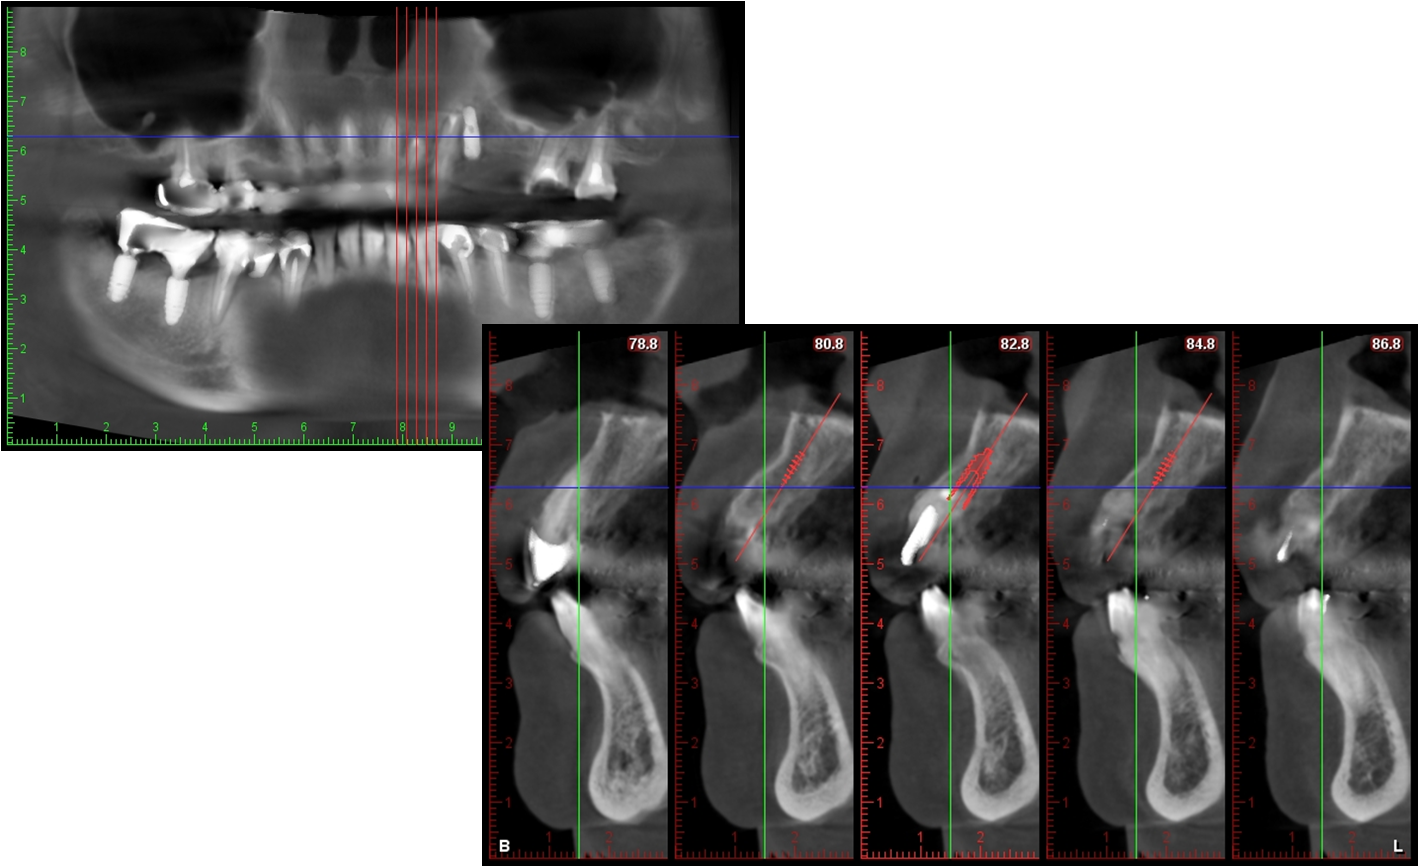

手術前電腦斷層評估